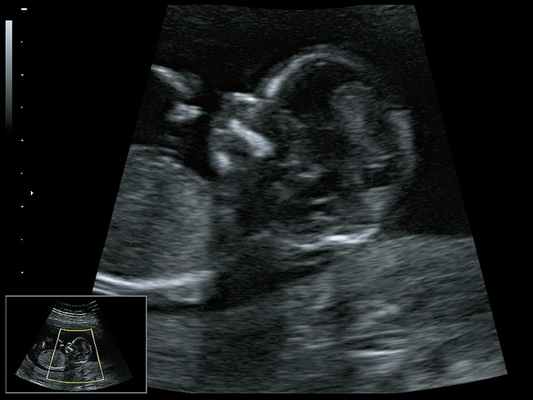

Тот же ребенок, показанный спереди вверху в информационном окне, теперь виден сбоку, с маленькими ушами и подбородком, который находится далеко позади.

При ультразвуковом исследовании выявлены множественные особенности лицевого фенотипа у плода: микрогнатия (рис. 2–4), треугольная форма лица (рис. 5), опущенные книзу глазницы и гипоплазия скуловых дуг (рис. 6, 7), аномальная форма и положение ушей (рис. 5, 7).

![Микрогнатия - сагиттальный скан в 2D, беременность 13 нед]()

Рис. 2. Микрогнатия - сагиттальный скан в 2D, беременность 13 нед.